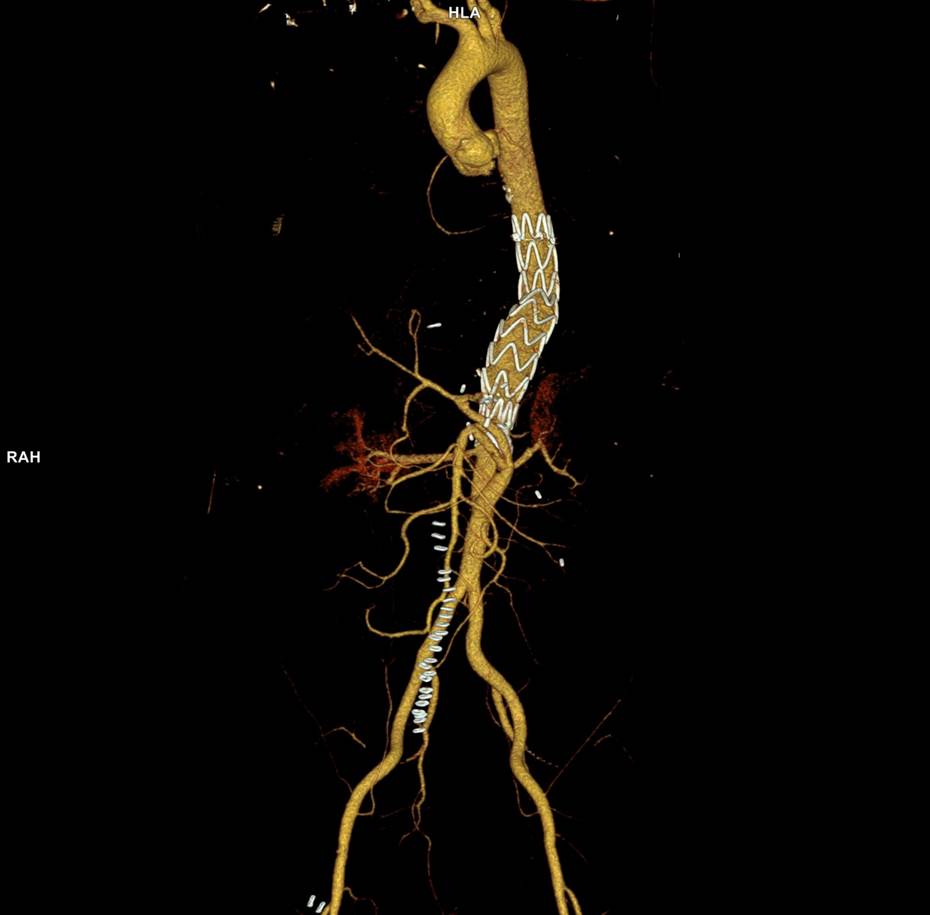

The patient is a middle aged man in his 50’s who presented with a type B aortic dissection. His dissection flap spanned from his left subclavian artery to the infrarenal aorta. He was a long time smoker and had hypertension that was difficult to control, made much worse after his dissection. He had a moderate dilatation of his thoracic aorta, maximally 36mm and tapering to 35mm in visceral segment. There was a 4.9cm infrarenal AAA where the dissection terminated.

His chest pain resolved with blood pressure control and he was discharged, but in followup his thoracic aortic segment grew and his blood pressure worsened, never getting below a 150mmHg systolic despite multiple agents. CTA two months after presentation, showed growth of his TAA to 44mm from 36mm in two months and the visceral segment showed that his dissection flap impinged on flow to the right renal artery. His AAA remained the same. He continued to have bouts of chest pain related to hypertension.

This patient needed a left subclavian artery debranching and then TEVAR of his dissecting thoracic aortic aneurysm, and intervention on his right renal artery. We did this in one setting performing first a left carotid subclavian artery transposition and then percutaneous TEVAR from the left common carotid artery origin to the supraceliac abdominal aorta.

The completion aortography showed good deployment of the CTAG device from the left common carotid artery origin to the celiac axis origin. The false lumen was no longer visualized. The right renal artery which was narrowed was treated with a balloon expandable stent.

He at 6 month post TEVAR followup, CTA showed stablility in his thoracic aorta. in infrarenal AAA grew from 5.0 to 5.7cm between the 1 month CT and the 6 month CT.

The terminus of the stent graft excluded the false lumen in the thoracic aorta but also resulted in filling and pressurization of the false lumen beyond and can be seen as a 44mm lateral dilation of the visceral segment of the aorta which had developed in the 6 month interval since the TEVAR.

The infrarenal neck continued the dissection and had dilated to about 36mm, but was parallel for a good length above the AAA. I decided to treat the inrarenal aorta with direct transabdominal repair. This would allow me to fenestrate the aorta, and possibly prevent further growth of the viseral segment while reserving the retroperitoneum for the visceral segment repair if it came to it. The neck diameter was 36mm.

His operation was performed via an anterior approach with the patient supine. A tube graft repair was performed expeditiously and included resecting the dissection flap up to the clamp. Care was taken to avoid injury to the renal stent. The proximal anastomosis went well – the dilated aorta yet had strong tissue strength. A felt strip was used to buttress the aortic side of the anastomosis. The estimated risk of paralysis was less than 1% and risk of death was less than 2%. The patient recovered uneventfully and went home on POD 5.

He did well in subsequent followup, having successfully quit smoking. He retired early on disability and was becoming more active, but the visceral segment dilatation was concerning. At 6 months post infrarenal AAA repair, he underwent CTA and it showed patent thoracic stent graft and infrarenal abdominal graft. The intervening visceral segment continued to enlarge and was now 46mm. The decision was to wait another interval 9 months to see if this would stabilize. The segment grew some more and was 49mm. He wanted to give it another 6 months and at that time, CTA showed further growth over 5cm, and he had developed some abdominal discomfort. He was taken to the operating room.

A four branch repair of the visceral segment thoracoabdominal aortic aneurysm was performed. The diaphragm was taken down and the stent graft was clamped as was the infrarenal tube graft. A premade Coselli graft was used to bypass to the right renal, SMA, celiac, and left renal in those order. The patient had a CSF drain for the case which was removed on postoperative day 2. He recovered rapidly and went home on postoperative day 6. His estimated risk of paralysis was about 2-5%, mitigated by a protocol centered on CSF drainage and blood pressure control. His risk of death was 5%. Telephone followup reveals the he is pain free at a month out and functional nearly at baseline.

This illustrates the notion that three smaller operations in an aggregate over three years achieved the equivalent of the single big open type II TAAA repair.